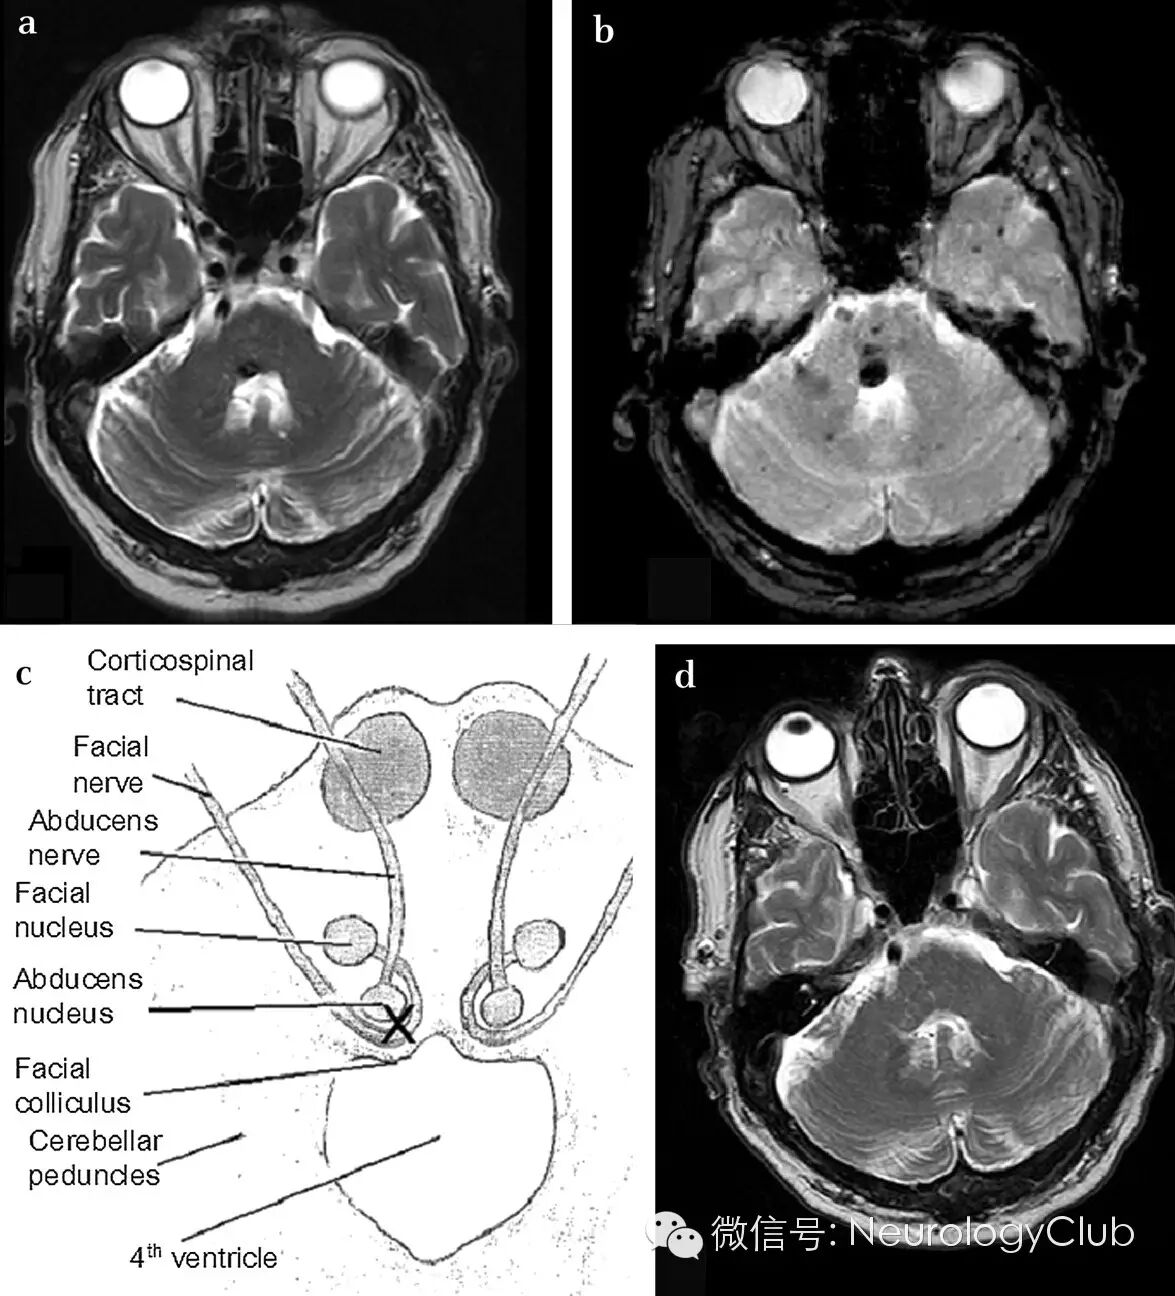

(A-B:嘴唇和躯干可见蓝色小结节,符合BRBNS的诊断;右侧周围性面瘫;C:皮肤活检提示真皮层扩张的血管,血管壁由单层内皮细胞排列形成)

(A:T2WI可见右脑桥背侧病灶;B:T2*上病灶呈低信号,符合静脉血和含铁血黄素沉积;C:“X”标记病灶,累及展神经核和面神经;D:4年前的MRI上未见静脉畸形